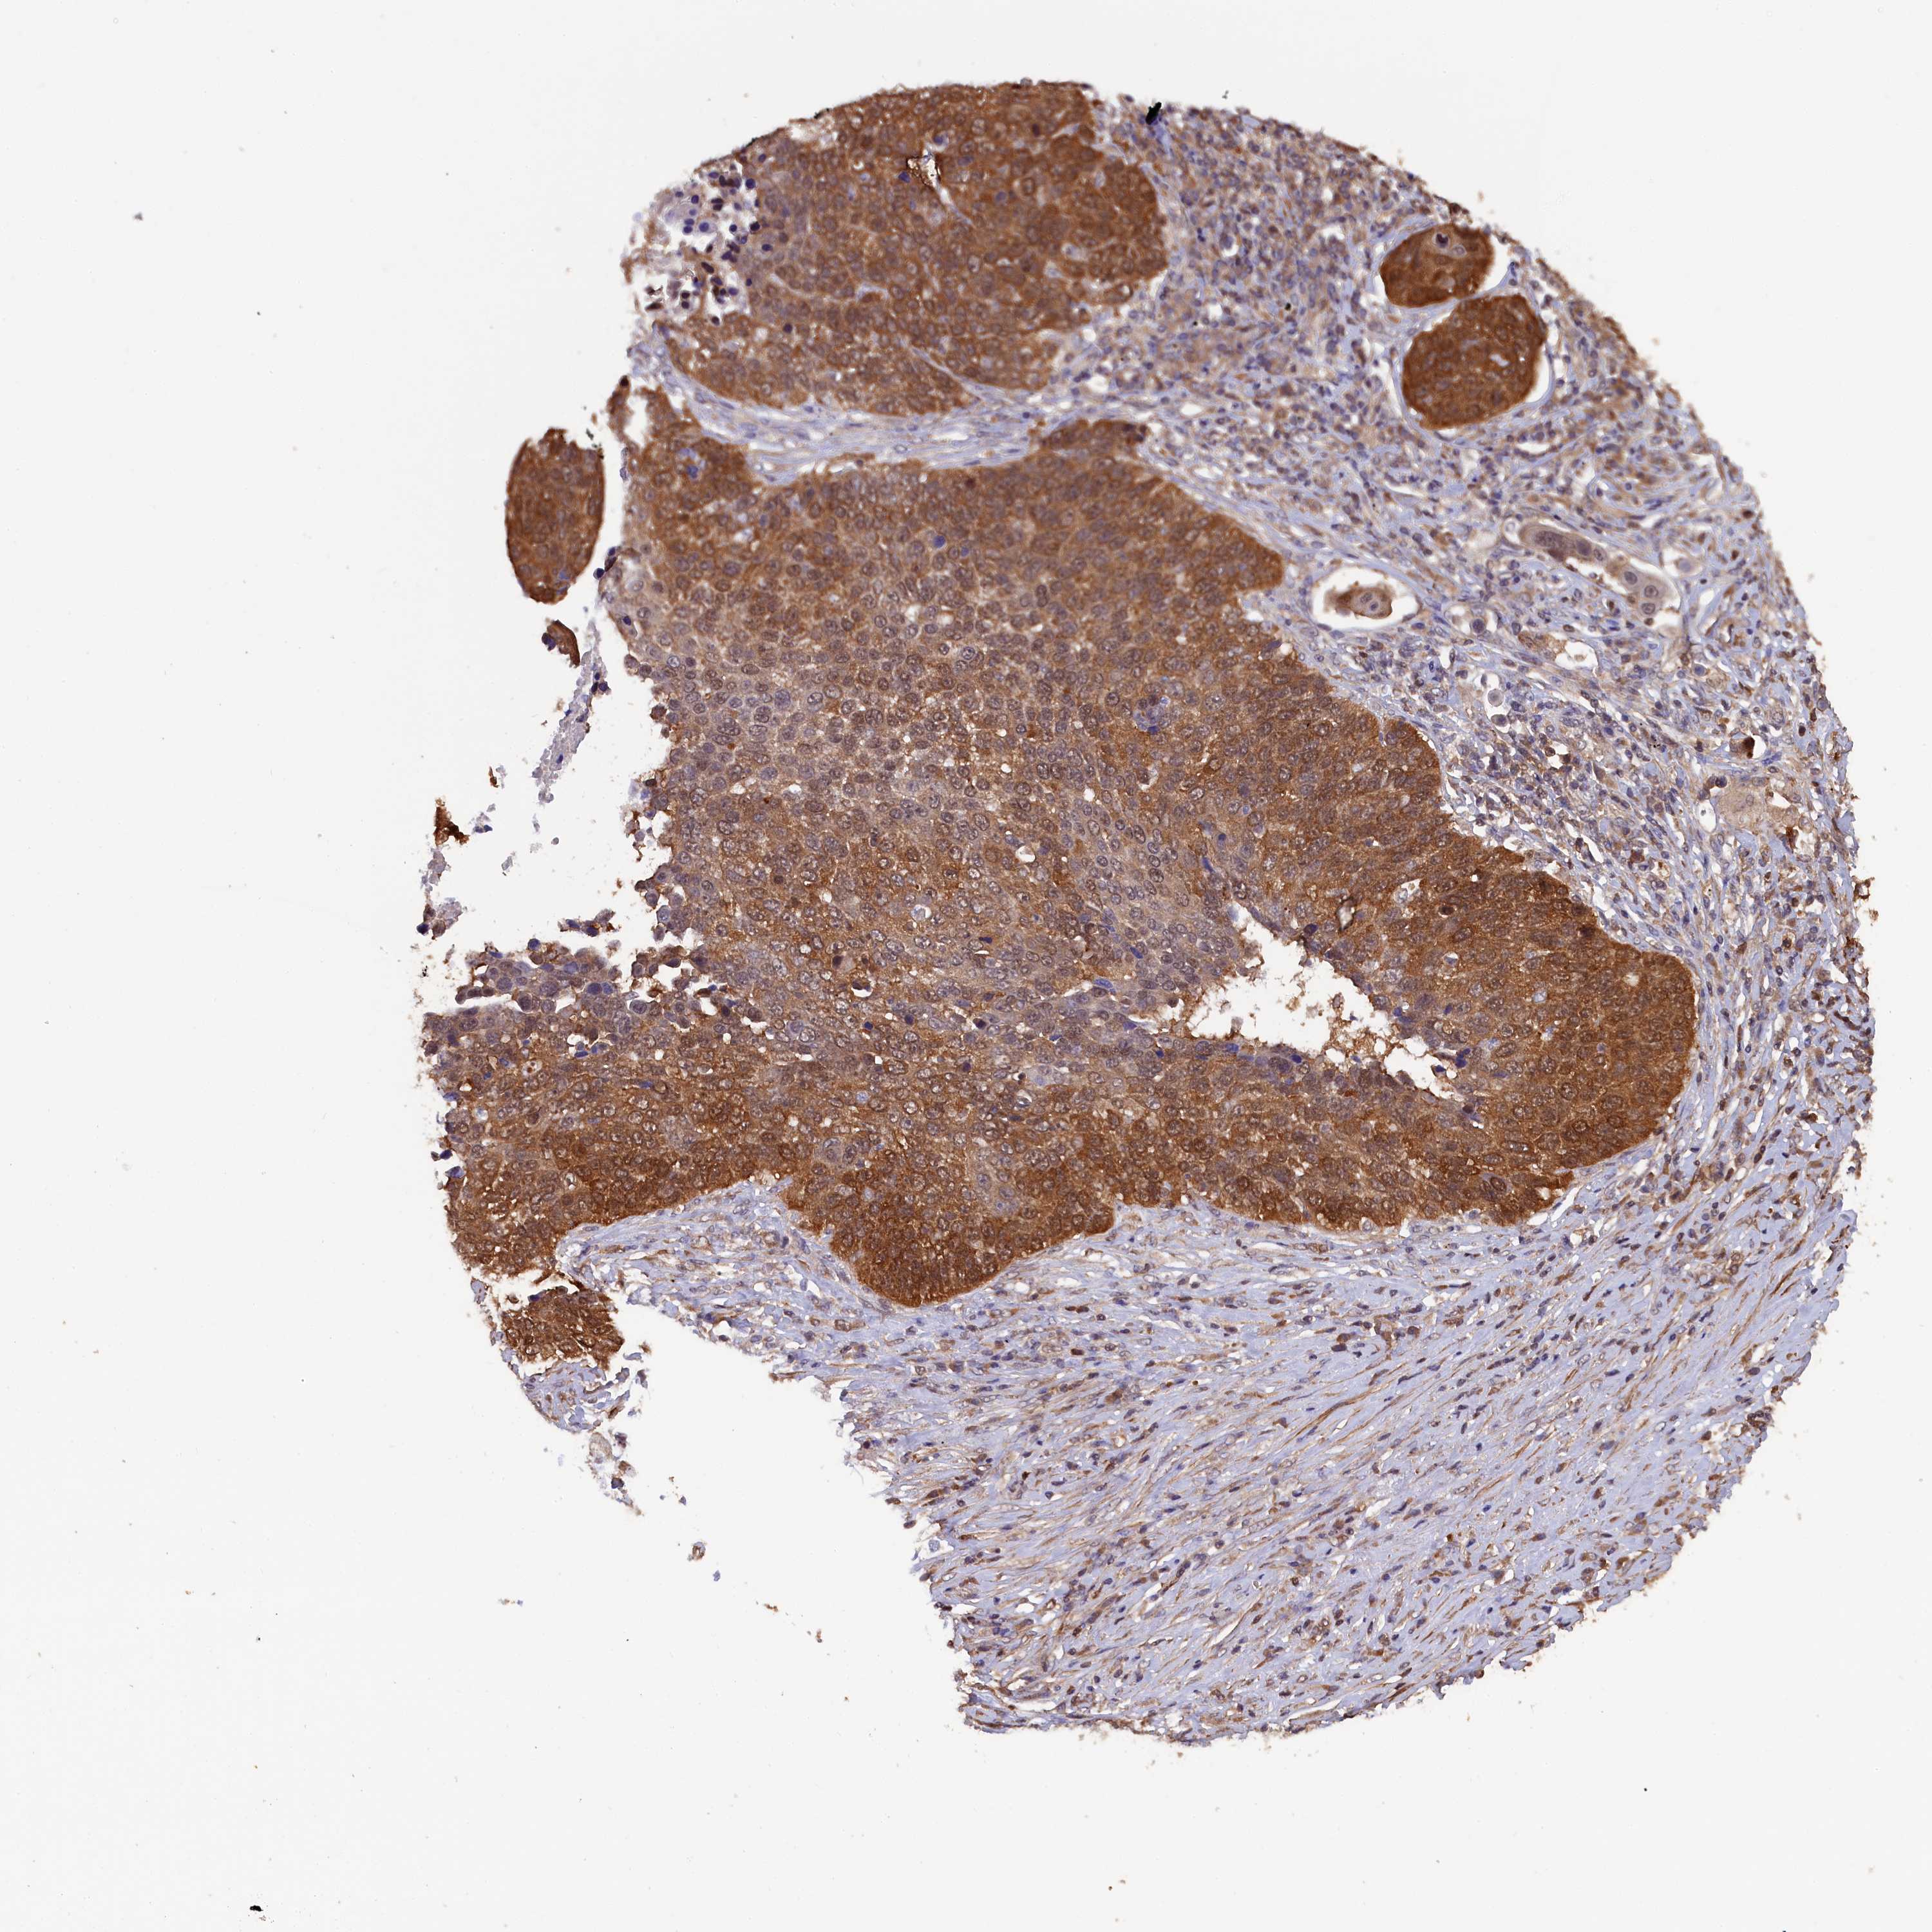

LUNG ADENOCARCINOMA (TCGA) - Interactive survival scatter ploti

The Survival Scatter plot shows the clinical status (i.e. dead or alive) for all individuals in the patient cohort, based on the same data that underlies the corresponding Kaplan-Meier plots. Patients that are alive at last time for follow-up are shown in blue and patients who have died during the study are shown in red.

The x-axis shows the expression levels (FPKM) of the investigated gene in the tumor tissue at the time of diagnosis. The y-axis shows the follow-up time after diagnosis (years). Both axes are complimented with kernel density curves demonstrating the data density over the axes. The top density plot shows the expression levels (FPKM) distribution among dead (red) and alive patients (blue). The right density plot shows the data density of the survived years of dead patients with high and low expression levels respectively, stratified using the cutoff indicated by the vertical dashed line through the Survival Scatter plot. This cutoff is automatically defined based on the FPKM cutoff that minimizes the p-score. The cutoff can be changed by dragging the vertical line or by entering a cutoff value in the square labeled "Current cut-off".

Under the Survival Scatter plot the p-score landscape (black curve; left axis) is shown together with dead median separation (red curve; right axis). Dead median separation is the difference in median mRNA expression between patients who have died with high and low expression, respectively. It is calculated as follows: median FPKM expression of dead patients with high expression - median FPKM expression of dead patients with low expression. This is intended to aid the user in visually exploring custom cutoffs and the associated p-scores and dead median separation.

Individual patient data is displayed and can be filtered by clicking on one or more of the category buttons on the top of the page. Categories describing expression level and patient information include: high, low, alive, dead, female, male and tumor stages. The scale of the x-axis can be toggled between linear and log-scale by clicking on the "x log" button. Mouse-over function shows TCGA ID, patient information and mRNA expression (FPKM) for each patient.

& Survival analysisi

Kaplan-Meier plots summarize results from analysis of correlation between mRNA expression level and patient survival. Patients were divided based on level of expression into one of the two groups "low" (under cut off) or "high" (over cut off). X-axis shows time for survival (years) and y-axis shows the probability of survival, where 1.0 corresponds to 100 percent.

JPT2 is not prognostic in Lung Adenocarcinoma (TCGA)

Best expression cut offi

Based on the FPKM value of each gene, patients were classified into two groups and association between prognosis (survival) and gene expression (FPKM) was examined. The best expression cut-off refers the FPKM value that yields maximal difference with regard to survival between the two groups at the lowest log-rank P-value. Best expression cut-off was selected based on survival analysis .

When clicking on this number, the vertical dashed line indicating cut-off, the interactive survival plot, and the Kaplan-Meier curve will be adjusted to show results based on the best expression cut-off.

: 53.18

P scorei

Log-rank P value for Kaplan-Meier plot showing results from analysis of correlation between mRNA expression level and patient survival.

N/A

Average pTPM 74.0

Number of samples 497